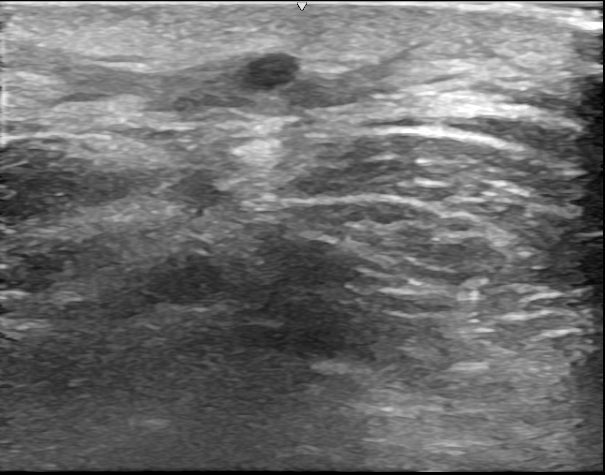

初回手術術中